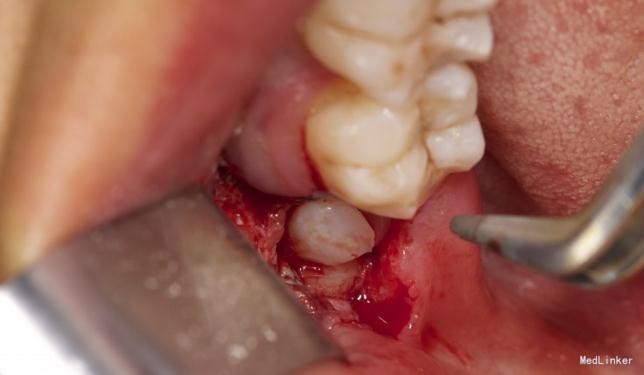

左下8水平阻生拔除

患者,男,25岁,要求拔除左下颌水平阻生牙齿,平素体质一般,无药物、食物过敏史,无高血压、心脏病等系统病史

拔除术